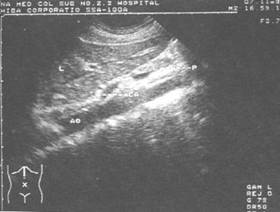

*腹主动脉纵切超声显像图——肝(L) 贲门(CA) 胰腺(P) 腹主动脉(AO